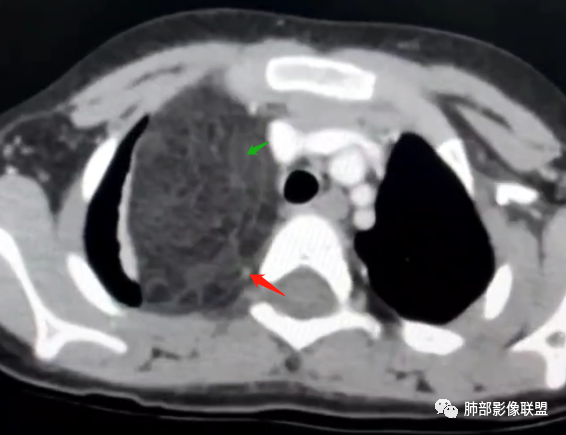

右上纵隔混杂密度肿块,边缘光整,与纵隔分界清,其内多发脂肪密度,增强无明显强化,其内血管穿行,考虑纵隔脂肪母细胞瘤,鉴别畸胎瘤,脂肪肉瘤。

患儿3岁 咳嗽检查发现纵隔占位。右肺上叶受压表现,占位以脂肪组织密度为主,似见分隔,首先考虑为脂肪母细胞瘤,鉴别脂肪瘤,畸胎瘤。

病灶属于交界区,主体位于肺内,占位效应明显,前方突入胸壁,胸腺受压变形,胸膜显示欠清楚;病灶包绕上叶肺动脉;似乎有体动脉供血。符合肺内的点:包绕上叶肺动脉分支;符合纵隔的点:前方似乎突入胸壁,与胸腺关系比较密切,但是与上腔静脉的关系提示病灶不支持纵隔来源,前纵隔的常规会将上腔静脉受压后移、外移,这是不符合的。

从这个角度符合肺内的,有一点不太踏实的是:似乎突入前胸壁。

手术记录:见右肺上叶肿物,肿物与右肺上叶关系密切。与纵隔无粘连,逐步分离肿物,见肿物大小约6cm*5cm,边界清楚,于右肺上叶粘连,边界清楚,肿物包绕右肺上叶血管及支气管。超声刀逐步游离肿物,完整切除肿物,右肺上叶肺组织无破溃,表面无出血。

2.肺动脉穿行也许是肺内来源最重要支持点!

CT扫描对脂肪类肿瘤常有独到价值。肿块孤立、边界清楚,未见周围浸润,较均匀脂肪样低密度,高度提示为良性!

发生于成人为脂肪瘤表现,婴幼儿自然会想到脂肪母细胞瘤。两者生物学行为并无本质区别。